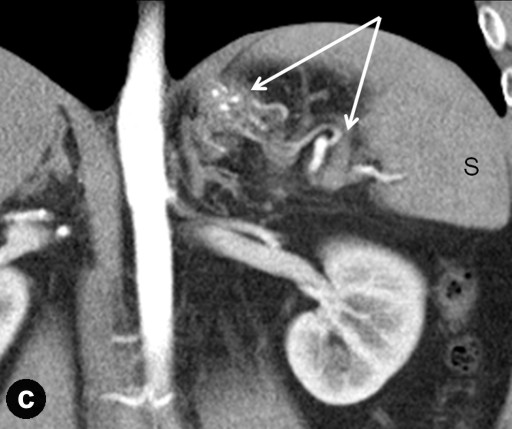

Preceding surgery, the splenic artery was always seen on CT angiography as a thick stem with no other branches travelling to the spleen (Figures 7a and 8a). As a consequence of splenic artery resection, the whole or the bulk of its trunk were no longer available for evaluation by CT angiography after a spleen-preserving distal pancreatectomy with resection of the splenic vessels and, in all 10 cases, the gastroepiploic arcade was seen to have become the “highway” to the spleen within 7-30 days after surgery (Figures 7b, 8b, and 9). In two cases, due to technical reasons, 3D CT angiography was only carried out postoperatively but, in both cases, there were no doubts about the source of the blood supply to the spleen (Figure 9). In none of the 10 cases was any appreciable blood flow through the short gastric arteries visualized.

Figure 9. Celiaco-mesenterial anatomy in 57 (a.) and 51 year old females (b.) women with mucinous cystic tumors of the pancreatic body and tail. 3D CT angiography 7 and 30 days, respectively, after a spleen-sparing distal pancreatectomy with resection of the splenic vessels without the renal artery images. The only vessels feeding the spleen are the gastroepiploic arcades (arrows). There are no other detectable collaterals of value. 3D CT angiography images were not obtained before surgery. |